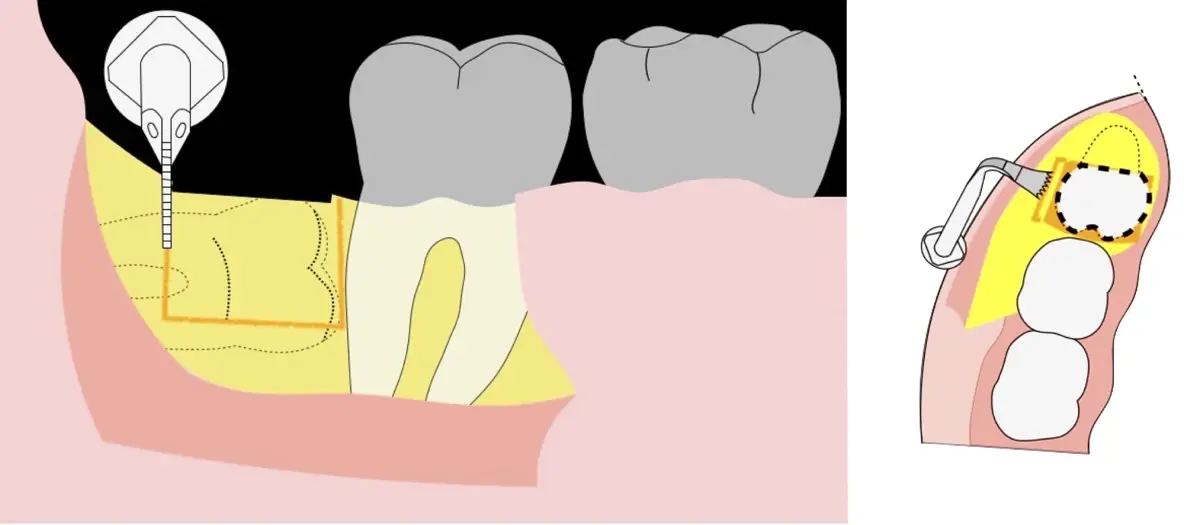

En contraste, el instrumento piezoeléctrico utiliza un corte micrométrico que retira un área de superficie mínima de hueso, y reduce el riesgo de termonecrosis marginal en comparación con las fresas rotatorias convencionales.9 Los micromovimientos mejoran la precisión en el corte y el control táctil, y eliminan las macrovibraciones que se producen con los instrumentos rotatorios.10 Su frecuencia de oscilación es la amplitud de 60-200 μm horizontalmente y de 20-60 μm en sentido vertical, lo que es muy inferior en comparación con las micro sierras oscilantes; por lo tanto, proporciona cortes de osteotomía precisos y seguros. Adicionalmente, posee vibraciones ultrasónicas que descomponen el líquido de irrigación en partículas muy pequeñas (fenómeno de cavitación, que produce un efecto hemostático y así reduce la pérdida de sangre), lo que proporciona una visión clara y sin obstáculos del campo quirúrgico11,12.

El procedimiento se inicia colocando anestesia troncular para bloqueo del nervio dentario inferior y sus ramas. Luego, se establecerá el diseño de acceso según la disposición de la molar a extraer. Para fines didácticos, se explicará cómo se realizaría la extracción de la molar de la Figura 1: se realiza una incisión horizontal a nivel de la zona retromolar hasta llegar a distal de la segunda molar, continuándose con una incisión intrasurcular hasta mesial de la segunda molar, finalizando con una incisión vertical a espesor total hasta llegar a la línea mucogingival (Figura 2).